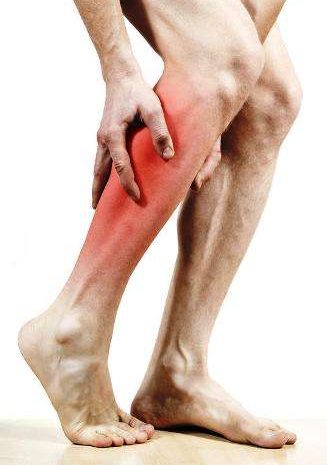

Muscular Injuries

Treating muscular conditions in the neck, shoulder, arms, back, hip and legs are a daily occurrence in Turnpike Clinic. Poor blood flow affects muscle pain though muscular pain occurs for many reasons, poor blood flow inside the muscle is a common cause (Tanaka, Mori et al. 2009). In order for the muscle to function, it must receive adequate blood flow. Compromised blood flow allows waste metabolic substances such as lactic acid to accumulate, resulting in muscle fatigue and pain and negatively affecting overall muscle endurance. Good blood flow enhances the removal of metabolic waste and allows the muscles to obtain more oxygen to perform their job.

Sufficient blood flow is also important to prevent injury. This is why it’s important to spend some time warming up before starting any serious physical activity.